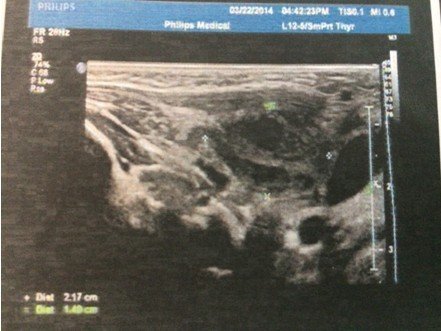

4个月大的婴儿,右颈部耳垂下方(2公分左右)有个硬疙瘩,婴儿无明显异常,吃奶睡觉等等一切正常,精神 状态很好,挂了3天的消炎水,图片为在2家医院做的B超,求解这个疙瘩是什么,需要怎么样治疗。医生叫继续挂消炎水进一步观察!(备注:B超2描述是:右侧颈部肌层后方探及22*15mm不均质低回声包块,其周围可见数枚低回声结节。 超声印象:右颈部包块伴周围淋巴结肿大。) 点击展开 匿名用户 2014-03-24 19:47 为您推荐: 其他回答 病情分析: 这个情况考虑是属于增生的症状, 指导意见: 你好,目前这个问题我建议及时消炎治疗,继续观察吧。 白其雨_6xwx 2014-03-24 21:36 相关问题 大夫您好我脖子右侧耳垂下方6公分左右 十五个月的宝宝耳垂前边脸颊上长了个长了个小疙瘩是怎么回事 十五个月的宝宝耳垂前边脸颊上长了个长了个小疙瘩是怎么回事

状态很好,挂了3天的消炎水,图片为在2家医院做的B超,求解这个疙瘩是什么,需要怎么样治疗。医生叫继续挂消炎水进一步观察!(备注:B超2描述是:右侧颈部肌层后方探及22*15mm不均质低回声包块,其周围可见数枚低回声结节。 超声印象:右颈部包块伴周围淋巴结肿大。)